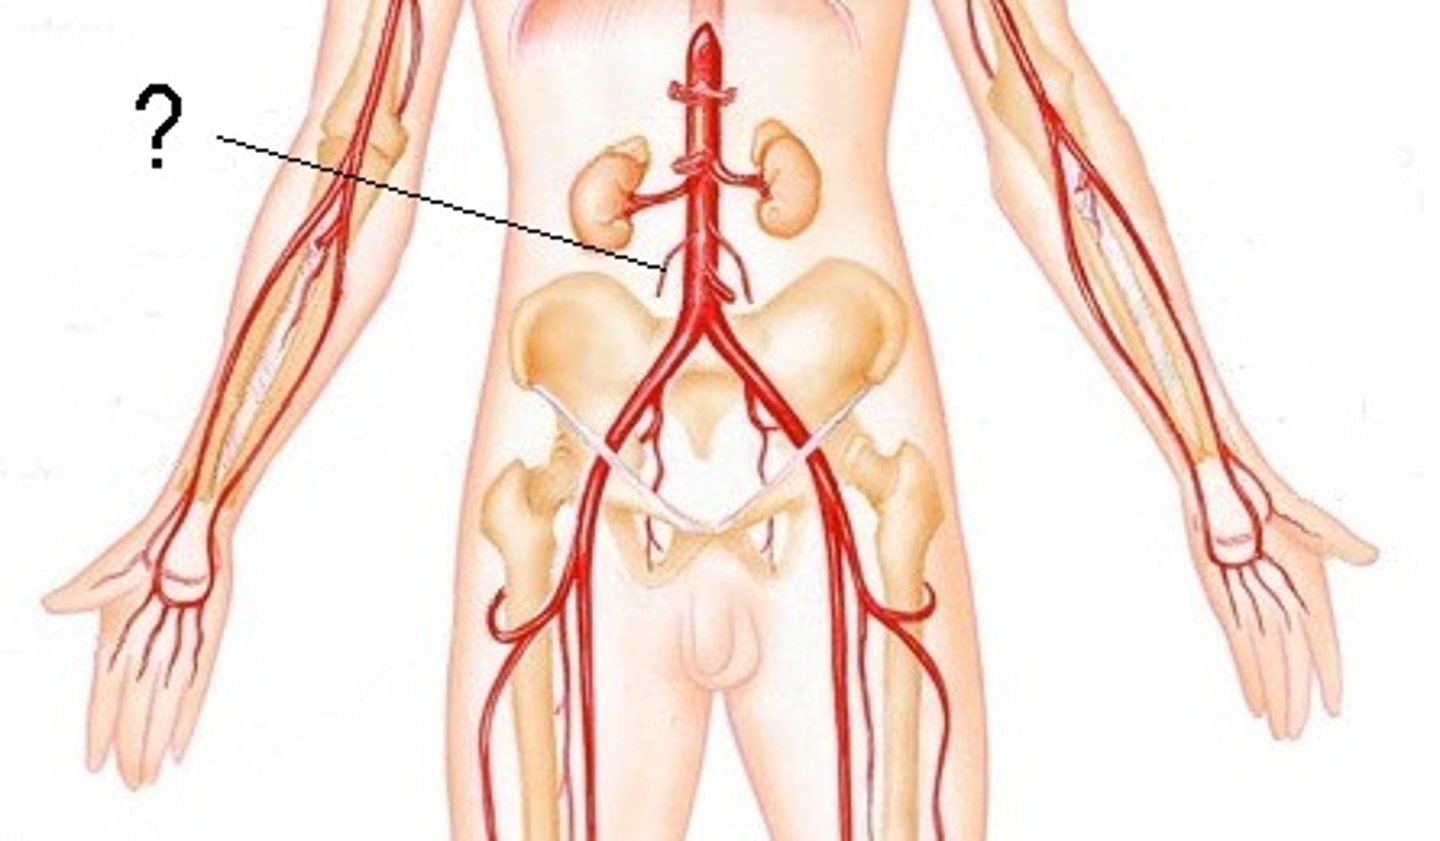

axillary artery

flows into axilla, lateral chest, and shoulder joint

brachial artery

flows into radial and ulnar arteries

radial artery

serves the lateral forearm, wrist, thumb, and index finger

ulnar artery

serves the medial forearm and digits 2-5

iliac artery

Serves the pelvic organs, lower abdominal wall, and lower limbs

femoral artery

serves the femur and thigh muscles

popliteal artery

feeds the posterior tibial artery, fibular artery, anterior tibial artery, and dorsalis pedis artery

anterior tibial artery

serves the muscles in the anterior compartment of the leg

posterior tibial artery

serves the muscles in the posteromedial part of the leg